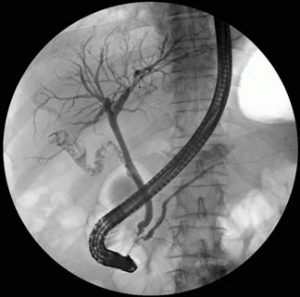

Imagem radiológica da árvore dos dutos biliares

O procedimento é realizado com o auxílio de um videoendoscópio (Sistema endoscópico com uma câmera na ponta) especial, chamado duodenoscópio, que possui visão lateral. Isto objetiva a visualização de um orifício existente na segunda porção do duodeno, chamada de papila duodenal ou de Vater. Através dela introduz-se um cateter com contraste, e utilizando-se um equipamento de raio-X Portátil, poderão ser visualizados os dutos biliares e pancreáticos.

Durante o exame as imagens radiológicas são interpretadas pelo médico endoscopista, muitas vezes assistido por radiologista. Dependendo do diagnóstico e da situação clínica, poderão ser realizados procedimentos adicionais visando tratamento, como a papilotomia (secção longitudinal da papila e seus pequenos músculos, visando ampliar o orifício de drenagem), retirada de cálculos com balão extrator ou cesta, dilatação de estreitamentos (estenoses) com balões ou sondas dilatadoras e drenagem biliar ou pancreática com emprego de próteses.